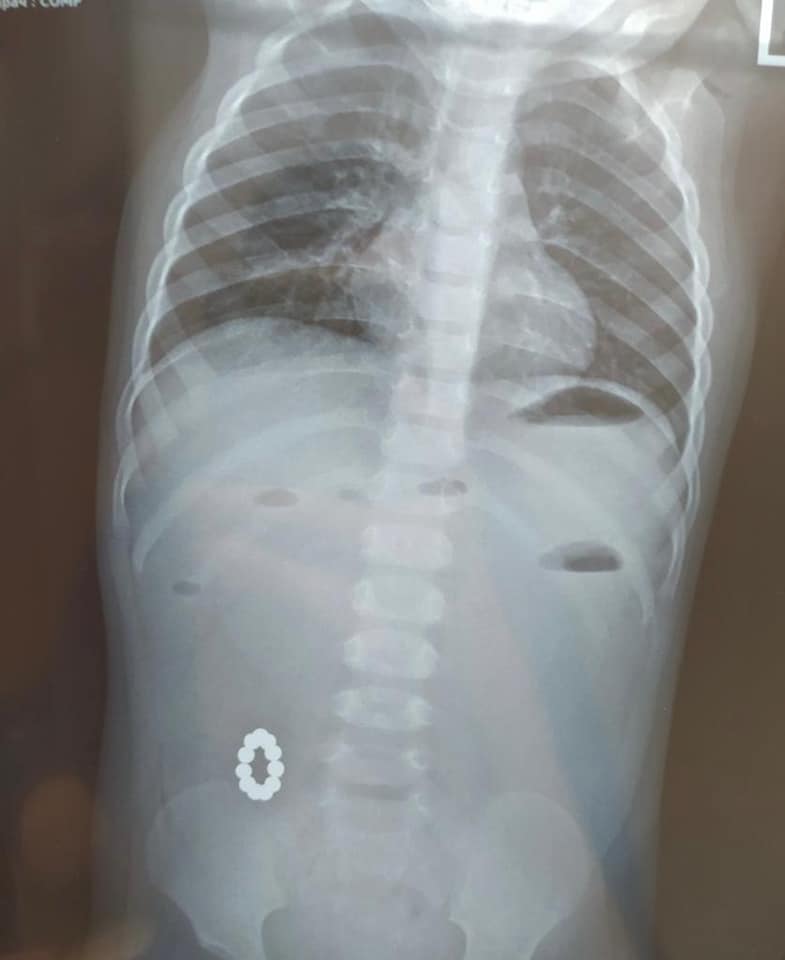

В Харькове девочка возрастом 1 годик попала в больницу, проглотив игрушку, особо опасную для маленьких детей. В итоге врачи успешно провели сложную операцию и извлекли посторонние предметы из кишечника.

В медучреждение маленький пациент попал с подозрением на пищевое отравление, но при диагностике обнаружили, что в кишечнике находятся магниты типа "Неокуб", которые соединились между собой и сложились в кольцо.

"На этот раз они привели к тяжелой хирургической патологии - непороходности кишечника! Мы уже не раз обращали внимание родителей на эти опасные игрушки особенно для малышей!" - отмечается в публикации.

Также в больнице опубликовали фото рентгена и самой игрушки, которую извлекли после операции.